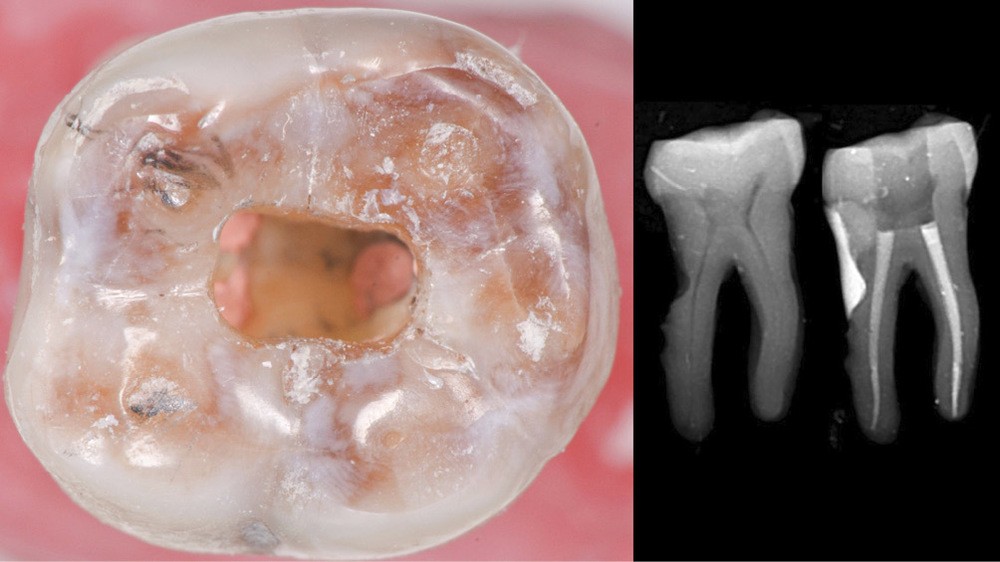

Trop large

Une cavité d’accès trop large optimiserait le pronostic endodontique mais compromettrait le pronostic biomécanique. C’est le cas de la cavité d’accès traditionnelle, qui a longtemps été « au service » du praticien réalisant le traitement canalaire (dentist-centered dentistry ou dentisterie centrée sur le praticien). Les étapes d’instrumentation, d’irrigation et d’obturation étaient ainsi facilitées grâce à des accès visuel et instrumental exagérés, aux dépens de structures dentaires saines (fig. 4).